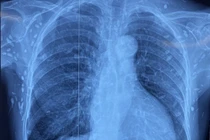

Sán dây lợn làm tổ trong não, phổi và dưới da người phụ nữ 77 tuổi